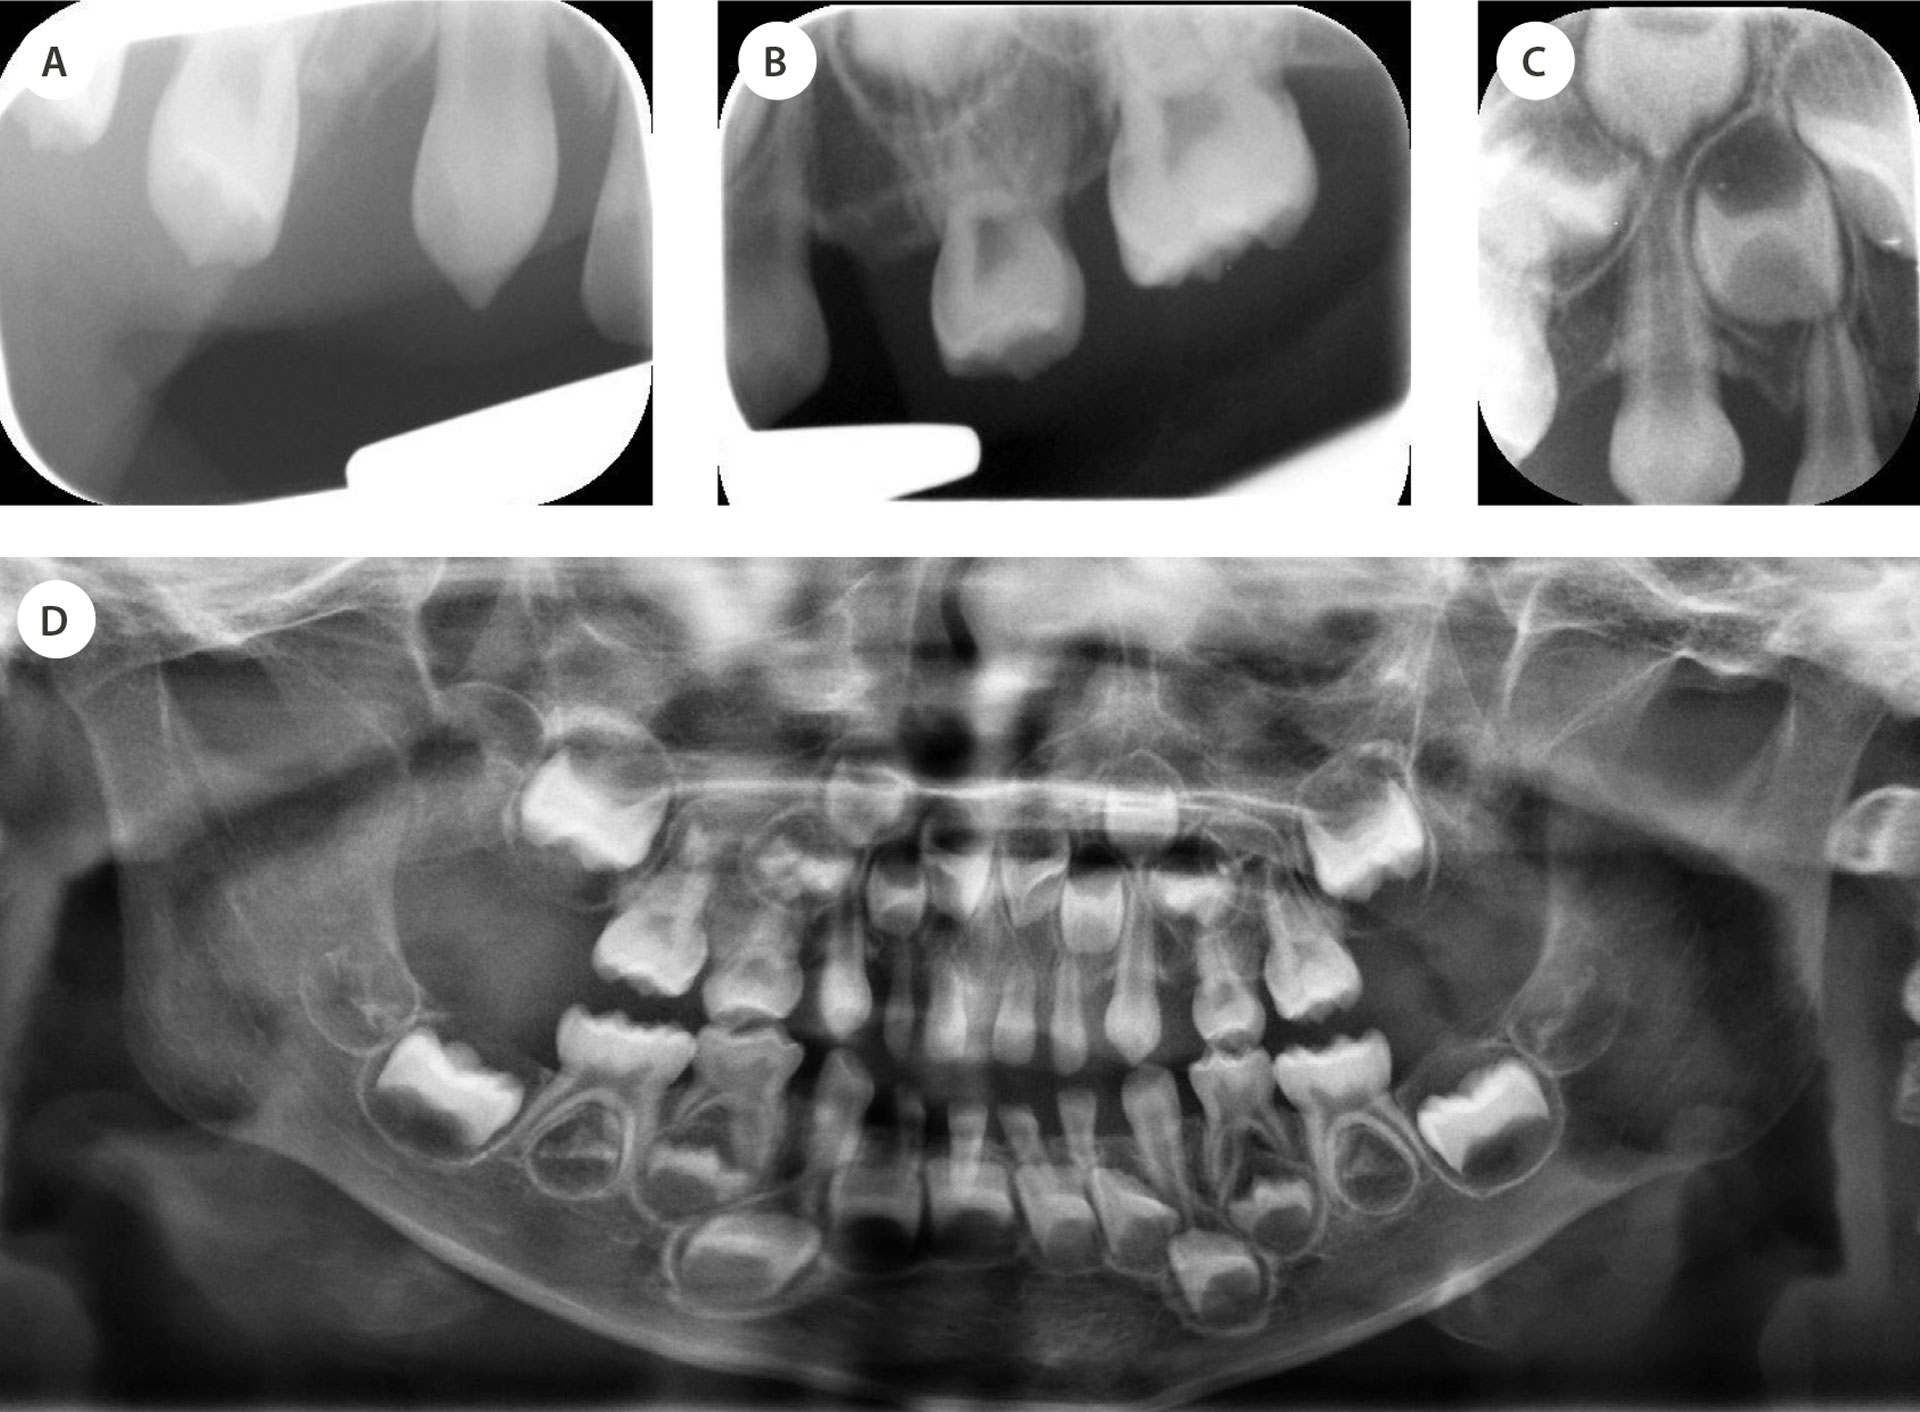

Periapikale røntgenbilder av sidesegmentene viste at tennene 55, 54, 53, 63, 64 og 65 var brutt gjennom ben med hele tannkronen (figur 2a–c). Pasienten hadde også et høyt festet labialt frenulum med vifteform, noe som gjorde overleppen stram og trakk den inn. I underkjeven var tennene 73, 72, 71, 81, 82 og 83 delvis dekket av gingiva. For tann 74 og 84 kunne man delvis se okklusalflaten, men glattflatene var ikke synlige. Selv om gingiva i underkjeven også var fibrøs og atypisk, var bildet ikke like uttalt som i overkjeven. Tannutviklingen på røntgen var forenlig med 4,5-årsalder og var dermed kommet lenger enn gjennomsnittet for pasientens alder [1].

Ved neste undersøkelse lyktes det å få tatt en orthopantomogram (OPG) (figur 2d). Her fant man marginalt bentap i fronten rundt tennene 52, 51, 61 og 62. Det ble valgt å ta et supplerende tannbilde regio 52 for å avgjøre om behov for eventuell ekstraksjon av 52 (figur 2b). Foresatte ble informert om festetap i overkjevens front og mulighet for prematur felling av incisivene og lateralene.

Figur 2. Røntgenbilder.

A., B. og C. Periapikale røntgenbilder av molarer og fronttenner i overkjeve.

D. Orthopantomogram (OPG).